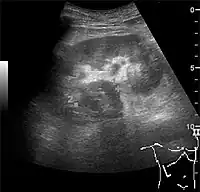

The hydronephrosis is typically graded visually and can be divided into five categories going from a slight expansion of the renal pelvis to end-stage hydronephrosis with cortical thinning (Figure 15). The evaluation of hydronephrosis can also include measures of calyces at the level of the neck in the longitudinal scan plane, of the dilated renal pelvis in the transverse scan plane and the cortical thickness, as explained previously (Figure 16 and Figure 17).[1]

Figure 15. End-stage hydronephrosis with cortical thinning. Measurement of pelvic dilatation on the US image is illustrated by ‘+’ and a dashed line.[1]